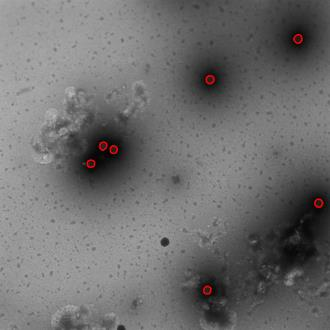

Regular monitoring of the primary particles and purity profiles of a drug product during development and manufacturing processes is essential for manufacturers to avoid product variability and contamination. Transmission electron microscopy (TEM) imaging helps manufacturers predict how changes affect particle characteristics and purity for virus-based gene therapy vector products and intermediates. Since intact particles can characterize efficacious products, it is beneficial to automate the detection of intact adenovirus against a non-intact-viral background mixed with debris, broken, and artefact particles. In the presence of such particles, detecting intact adenoviruses becomes more challenging. To overcome the challenge, due to such a presence, we developed a software tool for semi-automatic annotation and segmentation of adenoviruses and a software tool for automatic segmentation and detection of intact adenoviruses in TEM imaging systems. The developed semi-automatic tool exploited conventional image analysis techniques while the automatic tool was built based on convolutional neural networks and image analysis techniques. Our quantitative and qualitative evaluations showed outstanding true positive detection rates compared to false positive and negative rates where adenoviruses were nicely detected without mistaking them for real debris, broken adenoviruses, and/or staining artefacts.